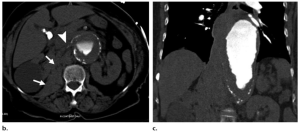

Hình 7. Tình trạng không ổn định của phình động mạch và vỡ động mạch được bao bọc lại (contained rupture) ở bệnh nhân nữ 60 tuổi mắc nhiều bệnh lý nội khoa—bao gồm hội chứng kháng thể kháng phospholipid, viêm tụy mạn và ung thư thực quản—và tiền sử hút thuốc lá, nhập viện vì đau bụng.

(a, b) Hình ảnh CT cho thấy tổn thương dạng dải (stranding) mới xuất hiện ở trong phúc mạc (intraperitoneal) và sau phúc mạc (retroperitoneal) (các mũi tên), khi đánh giá lại, được xác định là xuất huyết (hemorrhage) và kích thước phình động mạch ổn định (stable aneurysm size). Vào thời điểm đó, tình trạng đau của bệnh nhân được cho là do loét tá tràng chảy máu (bleeding duodenal ulcers).

(c) Hình ảnh CT theo dõi mặt phẳng axial thu được bằng thuốc tương phản đường tĩnh mạch 1 tháng sau đó cho thấy phình động mạch giãn ra nhanh chóng với xuất huyết quanh phình động mạch mới xuất hiện.

(d) Hình ảnh CT mặt phẳng axial được chụp lại do đau bụng nhiều hơn trong quá trình đánh giá tim mạch trước phẫu thuật cho thấy phình động mạch tiếp tục giãn ra với xuất huyết trong thành động mạch, biểu hiện bằng dấu hiệu hình liềm và tụ máu quanh phình động mạch, các dấu hiệu phù hợp với tình trạng không ổn định của phình động mạch và vỡ động mạch được cấu trúc xung quanh bao bọc lại (contained rupture), được xác định lúc phẫu thuật.